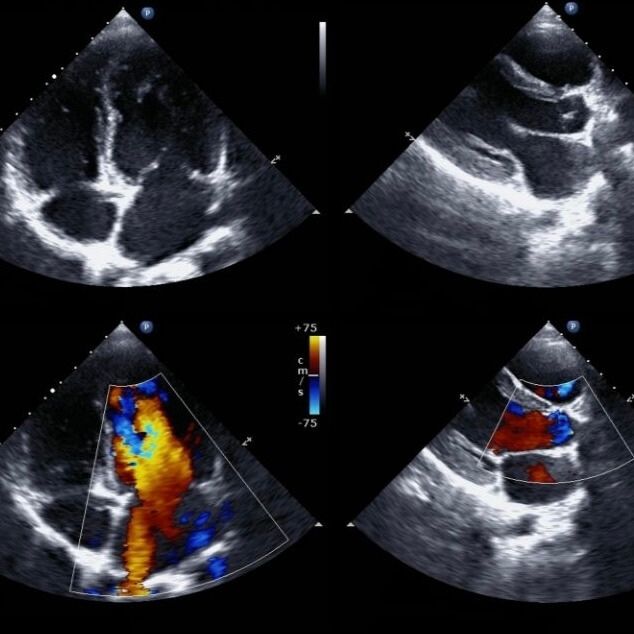

Die Auswertung erfolgt simultan zur Untersuchung. Es werden Veränderungen in der Herzgröße, die Dicke der Herzwände, die Pumpfunktion des Herzens ebenso wie die Entspannungsfunktion des Herzmuskels ermittelt. Besonders bei der Doppler-Echokardiografie ist es wichtig, den Blutfluss durch die Herzklappen zu überprüfen, um eventuelle Klappenfehler zu graduieren.

Wie wird der Blutfluss in der Echokardiografie gemessen? |

Der Blutfluss wird mittels Doppler-Echokardiografie. |